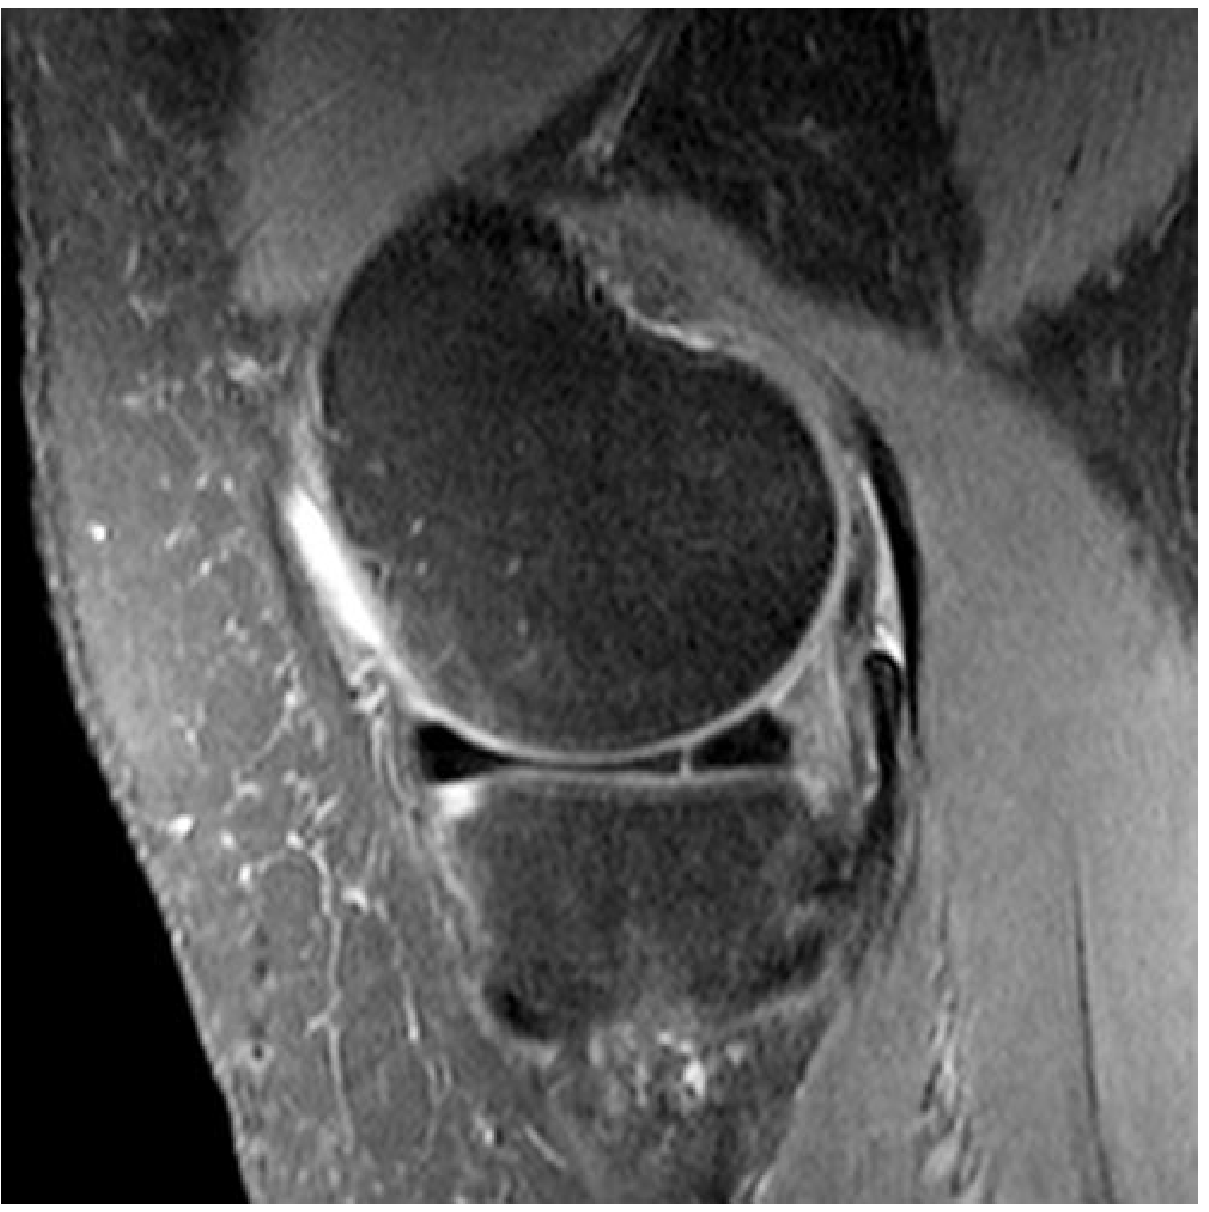

Fragment-in-Notch Sign (Coronal)

Displaced dark low-signal fragment sitting in the intercondylar notch; peripheral meniscus appears truncated.

Coronal MRI — flipped bucket-handle fragment of medial meniscus within the intercondylar fossa (arrow); peripheral meniscus is truncated

Bucket-handle tear — fragment-in-notch sign, coronal view (Grainger & Allison's Diagnostic Radiology)